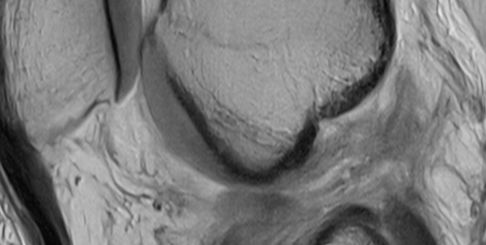

De entre todos los dolores de espalda, los más comunes e incapacitantes son las lumbalgias. Las revisiones epidemiológicas han comprobado que entre seis y ocho de cada diez personas sufrirán esta molestia en algún momento de su vida. Según la guía de manejo de las enfermedades más frecuentes de consulta en atención primaria de la Comunidad de Madrid, en más del 85% de quienes la sufren no se encuentra una causa subyacente. Son lo que se consideran dolores inespecíficos, que no dejan ninguna huella biológica que permita diagnosticarlos. La mayoría (el 90%) pasan a las seis semanas y, en contra de lo que se ha pensado durante mucho tiempo, el reposo total no suele ser un buen aliado.

Tumores, lesiones nerviosas, hernias, infartos renales, artritis inflamatorias, infecciones de hígado, inflamación en los tiroides son enfermedades detrás de algunos dolores de espalda que pasan por la consulta médica. Son parte de ese pequeño porcentaje que no responde a las causas habituales, y al que los médicos tienen que prestar especial atención.